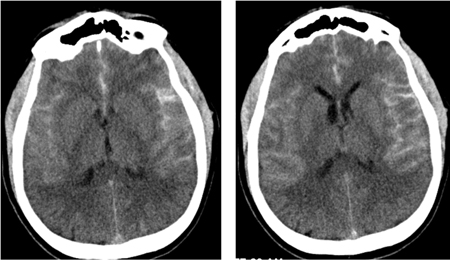

CT: thin cuts should be ordered (3-5 mm); otherwise, small, thin collections of blood might be missed. Subarachnoid blood will appear hyperdense (white) in the basal cisterns, major fissures, and sulci.[53] Detection of SAH on CT depends on density of blood, quantity of SAH, and timing of CT from ictus. A small quantity of blood in the subarachnoid space may be missed, and blood with hemoglobin below 10 g/dL may not be visible.[53] Nonetheless, the advent of third-generation CT scanners has dramatically improved the sensitivity of detecting subarachnoid blood, reaching 100% when performed within 6 hours of headache onset and read by experienced neuroradiologists.[54][55][56] The aneurysm rupture site can be predicted, though inconsistently, from patterns of blood accumulation on CT (thick collection in fissures) or parenchymal hematoma.[57][Figure caption and citation for the preceding image starts]: CT brain showing subarachnoid hemorrhage from a ruptured posterior cerebral artery aneurysm (1 of 2)Courtesy of Dr Salah Keyrouz; used with permission [Citation ends].CT brain showing subarachnoid hemorrhage from a ruptured posterior cerebral artery aneurysm (1 of 2)[Figure caption and citation for the preceding image starts]: CT brain showing subarachnoid hemorrhage from a ruptured posterior cerebral artery aneurysm (2 of 2)Courtesy of Dr Salah Keyrouz; used with permission [Citation ends].CT brain showing subarachnoid hemorrhage from a ruptured posterior cerebral artery aneurysm (2 of 2)